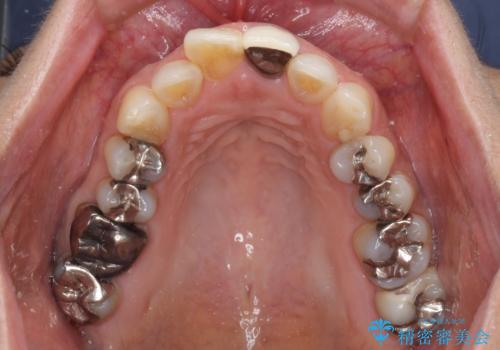

- 上下の奥歯にものが挟まりやすいことを気にして来院された患者様です。

上下ともに、やや大きいむし歯があり、そこにものが挟まりやすくなっていました。

上顎の奥歯は神経にまで虫歯が及んでいる可能性が高かったため、抜髄や断髄の可能性を考慮しながら処置を進め、セラミッククラウンにて補綴することとしました。